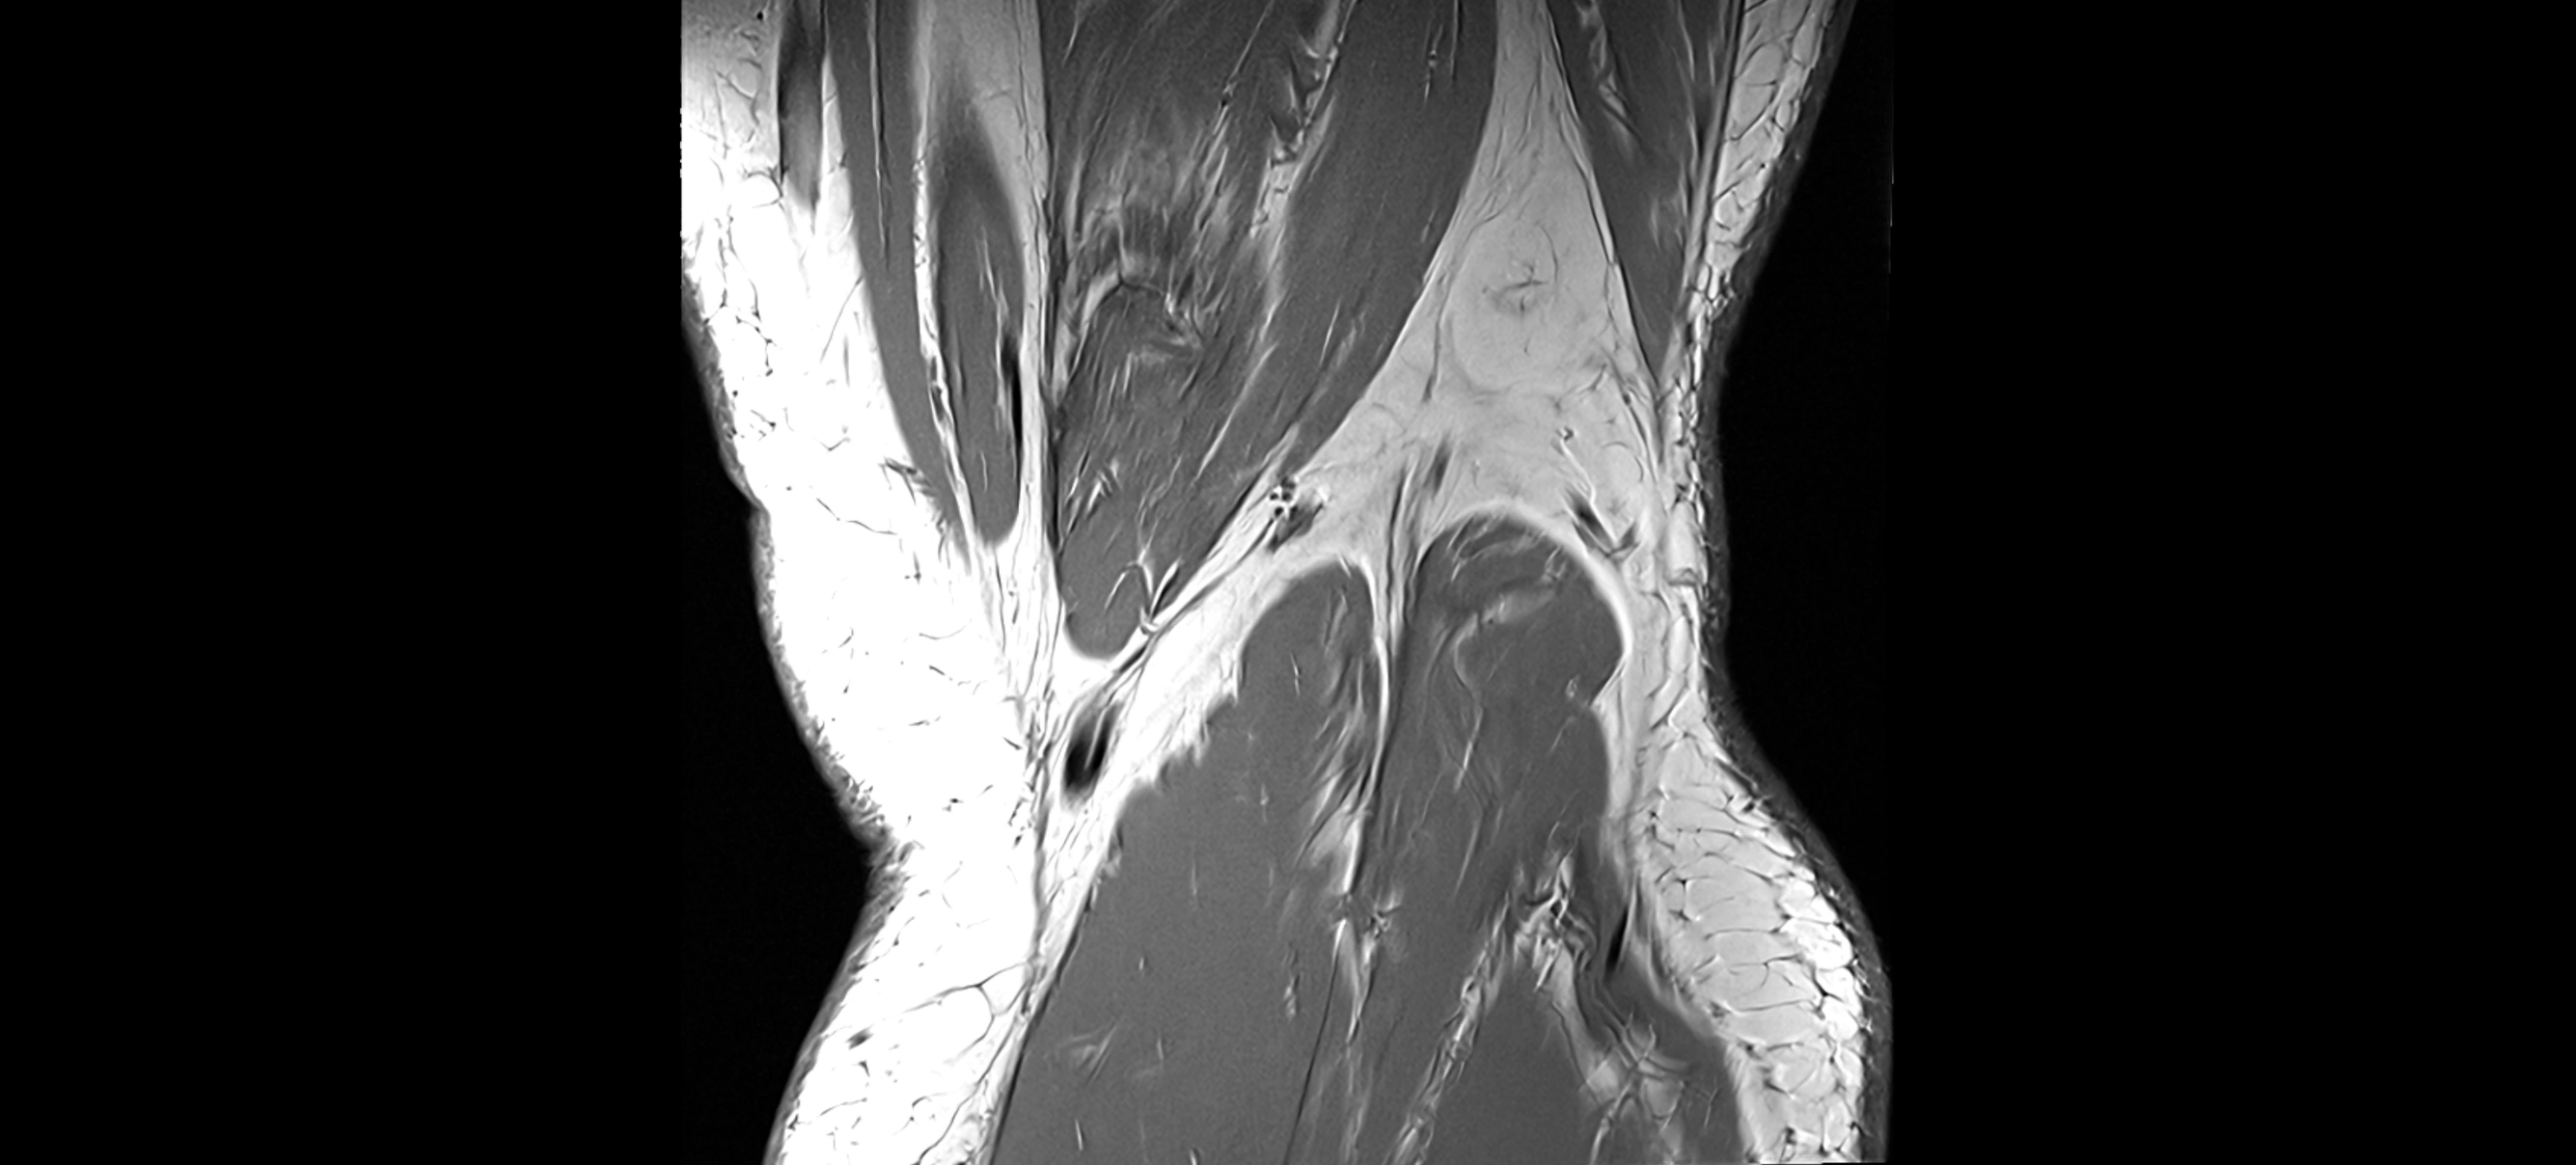

MRI Appearance

T1-weighted images:

• Normal ACL appears as a low-signal band-like structure crossing the intercondylar notch

• Surrounded by intermediate signal synovial fluid and fat planes

T2-weighted images:

• Normal ACL remains low signal

• Partial or complete tears appear as discontinuity, increased signal, or fiber laxity

STIR (Short Tau Inversion Recovery):

• Normal ACL shows dark low signal

• Acute injury shows bright hyperintensity due to edema and hemorrhage

Proton Density Fat-Saturated (PD FS):

• Normal ACL: dark, low-signal band

• Tears: bright intraligamentous hyperintensity, discontinuity, or abnormal course

MRI images

image